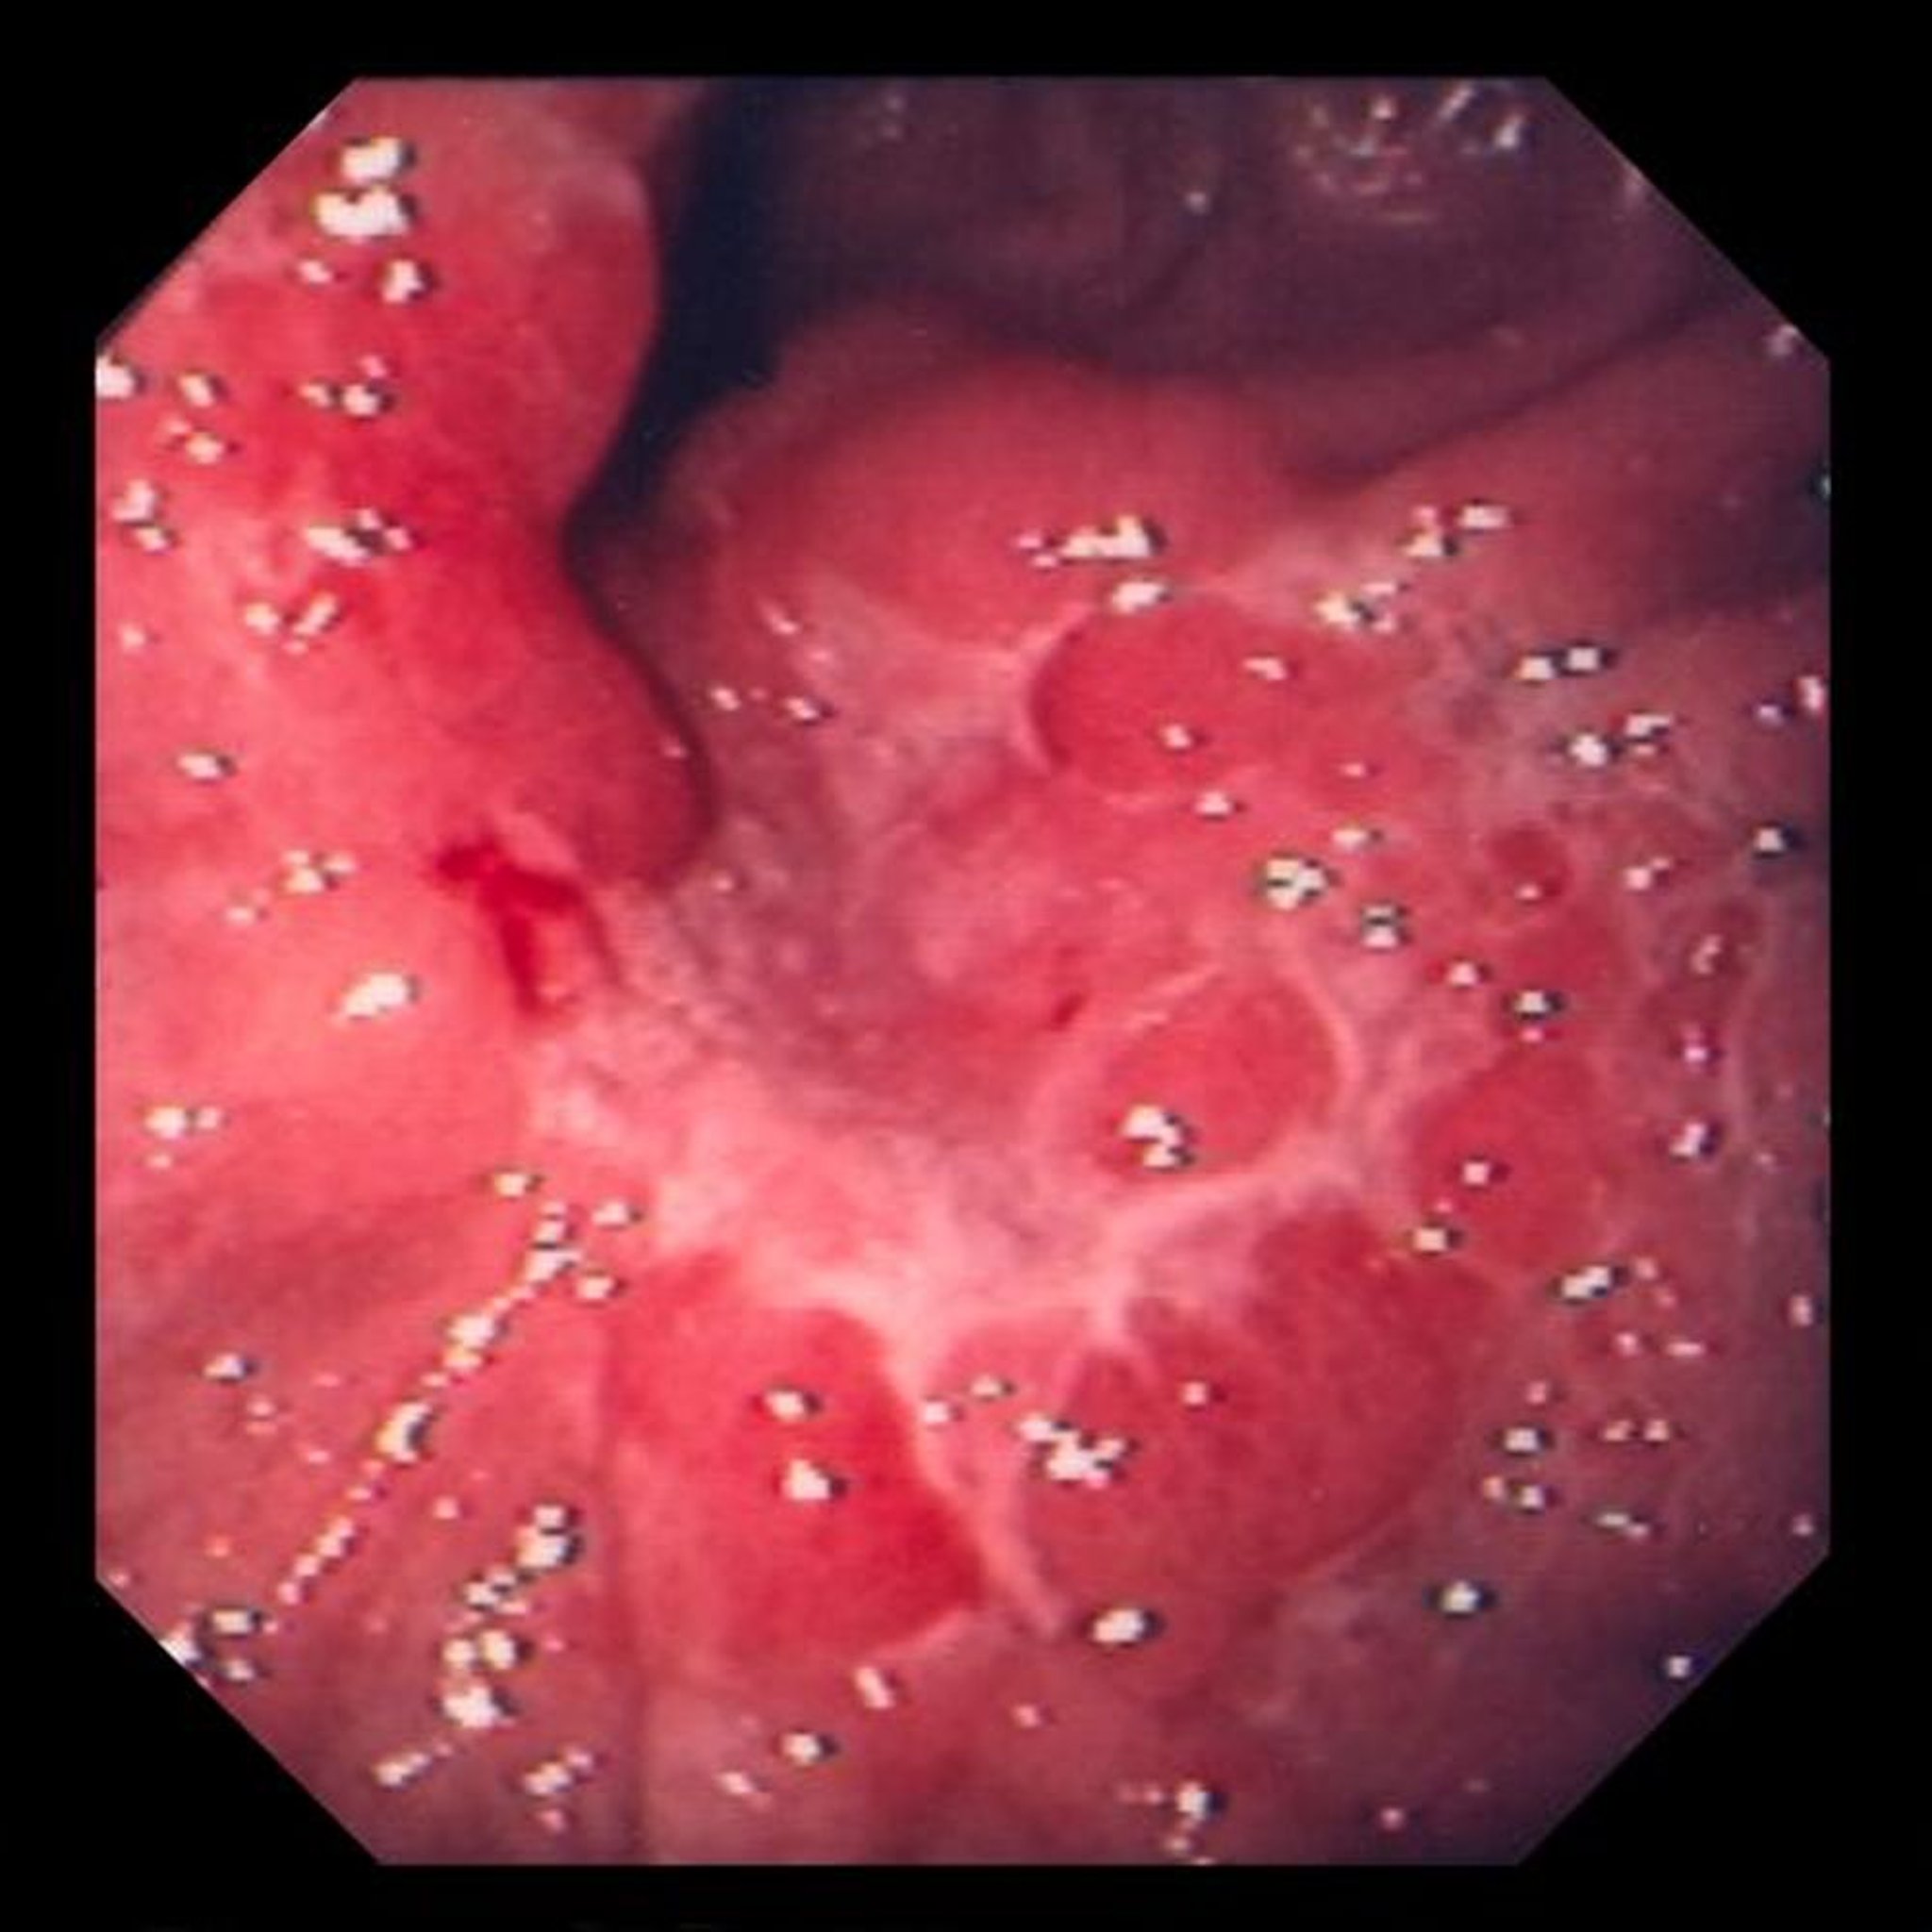

Essa imagem mostra uma úlcera no interior de pregas mucosas edemaciadas que, na biópsia, revelaram ser um adenocarcinoma pouco diferenciado (tipo celular em anel de sinete).

Image provided by David M. Martin, MD.